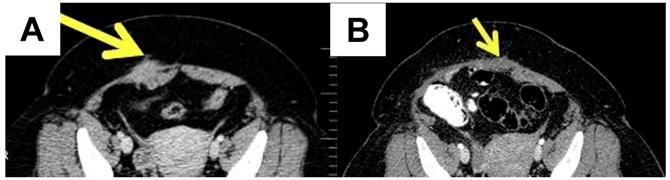

If AWE is suspected, the most useful assessment tools are ultrasound, computed tomography (CT) and magnetic resonance imaging (MRI) of the abdomen, including the abdominal wall (Figure 2).

MRI is better used in cases with small lesions, while CT provides better results in cases with muscle and subcutaneous layer involvement [36]. Ultrasound remains the best screening method [37]. The mean diameter of the AWE was 4.7 ± 1.53 cm in one retrospective observational cohort study [38]. The lesions of AWE have an isoechoic or hyperechoic pattern (46.7%), with peripheral vascularization (61.5%) on ultrasound and are homogenous and hypervascular on CT scan [39]. MRI is the most commonly used method for evaluating pelvic endometriosis. It is also used for preoperative disease staging [40].

A case of a 44-year-old female diagnosed with abdominal wall endometriosis 14 years after a caesarean section. She had chronic pain unrelated to the menstrual cycle. A. Preoperative aspect: computed tomography showing a poorly defined tumour of 3.9 cm at the abdominal wall, with a heterogeneous aspect. B. Post-operative aspect by computed tomography.